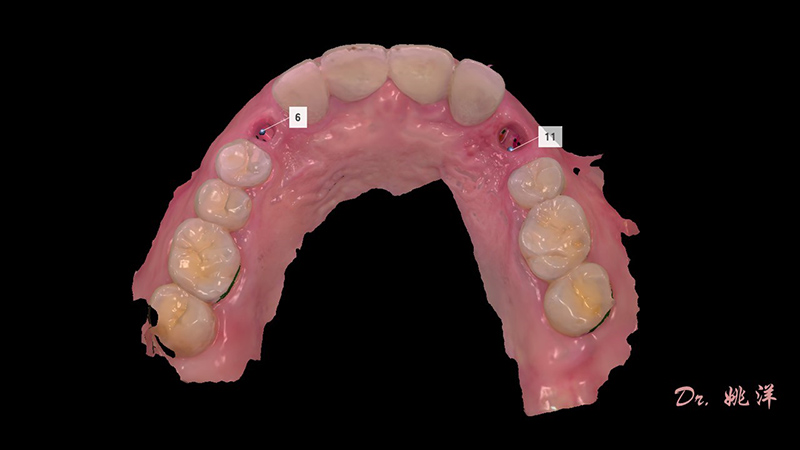

種植后數(shù)字化取模,前牙美學(xué)間隙精確分配

從最終修復(fù)效果可以看出:23,24間隙不足修復(fù)兩顆,修復(fù)為1顆牙。因?yàn)榻?jīng)過(guò)數(shù)字化設(shè)計(jì)和精確導(dǎo)航植入,修復(fù)體齦緣協(xié)調(diào)自然